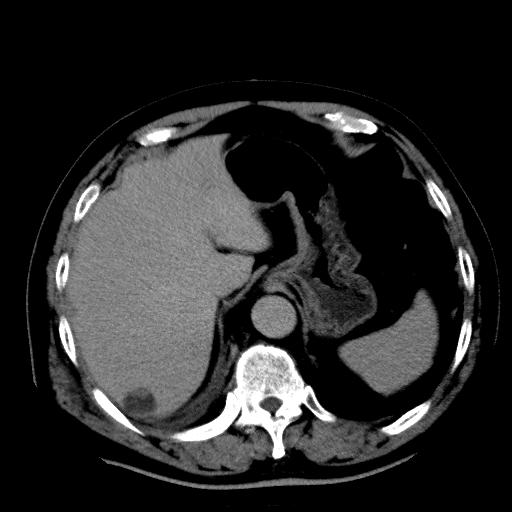

以下是引用zhctwbh在2008-8-23 14:20:00的发言:[br]囊肿合并出血

以下是引用zjb在2008-8-23 16:41:00的发言:[br]囊肿并出血可能性大。